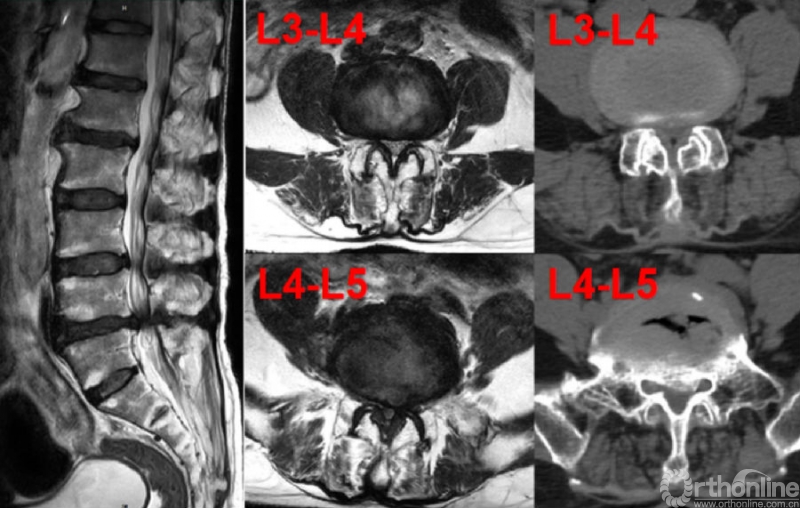

患者王先生,59岁,10余年前活动后出现腰部疼痛,休息后可缓解,近3年来活动后腰痛反复伴双下肢麻木疼痛,疼痛放射至双侧小腿前内侧、后外侧及足背,以右侧为著,行走距离缩短至300米,休息后症状稍缓解,保守治疗3月无效,严重影响其日常生活与工作。5月初,王先生来到首都医科大学附属北京友谊医院就诊。专科查体显示:双下肢感觉、肌力正常,腱反射对称引出,病理征(-),双侧直腿抬高试验及加强试验(-)。影像学检查提示腰3-4、腰4-5双节段腰椎管狭窄,其中腰4-腰5节段伴有椎间盘突出及钙化(图1)。患者症状、体征与影像学表现相符,L3-4、L4-5双节段腰椎管狭窄症诊断明确

图1.患者术前影像学(MRI+CT)检查结果